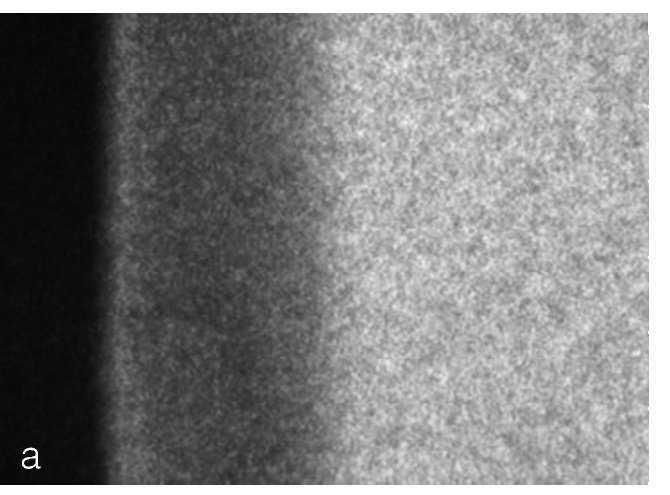

Numerosos estudios in vitro2,26 proclamaban que, con la aplicación frecuente de preparados con bajo contenido de fluoruro, se lograba una remineralización más adecuada que con la aplicación menos frecuente de productos con una alta concentración de fluoruro. Sin embargo, los geles y barnices con alta concentración de fluoruro tienen un efecto clínico de prevención de la caries independientemente de si los pacientes se cepillan o no los dientes con un dentífrico con fluoruro. En un trabajo de revisión del año 2001, Hellwig y Lussi10 constataron que no existe ninguna concentración de fluoruro óptima y universalmente válida que permite lograr la remineralización. Llegaron a la conclusión de que, clínicamente, lo que se consigue en cualquier caso con la acción del fluoruro es una estabilización de la zona externa de la lesión de caries incipiente más que una curación completa y real (fig. 2). En un nuevo estudio in situ de Altenburger et al1 se demostró con contundencia que, mediante la aplicación de preparados de fluoruro de alta concentración, se consigue una remineralización. Este estudio in situ aleatorizado de doble ciego, controlado con un placebo y de diseño cruzado, mostró que, mediante una sola aplicación de una solución con una alta concentración de fluoruro (Elmex fluid, Gaba, Lörrach: fluoruro al 1,0%), se lograba una mineralización notablemente mayor de las lesiones de caries incipiente en un periodo de 4 semanas en comparación con una solución con fluoruro al 0,5% y con una solución placebo (figs. 3a y 3b).

Figura 3a. Lesión de caries incipiente en microrradiografía transversal. El área gris oscuro está desmineralizada.

Figura 3b. Mineralización en este tipo de lesiones de caries incipiente después de una aplicación única de soluciones de fluoruro de diversa concentración. Se puede apreciar claramente que, cuanto mayor es la concentración de fluoruro, más intensa es la mineralización.